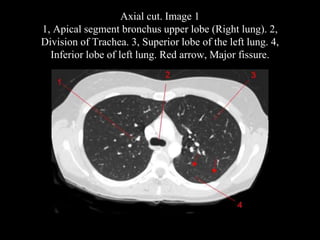

The document discusses the anatomy of the chest x-ray and CT scan by describing the lobes of the lungs and their locations. It also mentions the heart, mediastinum, hilum, and ribs. Several axial, coronal, and sagittal CT images are included with labels pointing out structures like the trachea, bronchi, lobes of the lungs, and fissures. In summary, the document provides an overview of lung and chest anatomy as seen on x-rays and CT scans through text descriptions and labeled medical images.